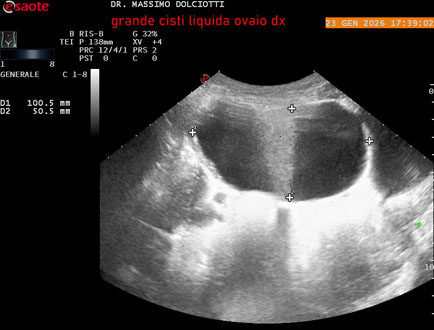

Età Paziente: F 29 anni

Motivazione dell'esame: dolore al lato destro della pelvi in portarice di cisti liquida all'ovaio destro.

Commento all'esame: le immagini ed il video documentano, in sede pelvica, grande formazione anecogena, delle dimensioni di 110 x 60 mm, priva di vascolarizzazione, da ricondurre a grande cisti liquida dell'ovaio destro.

Conclusioni: grande cisti liquida all'ovaio destro (large fluid cyst on the right ovary).